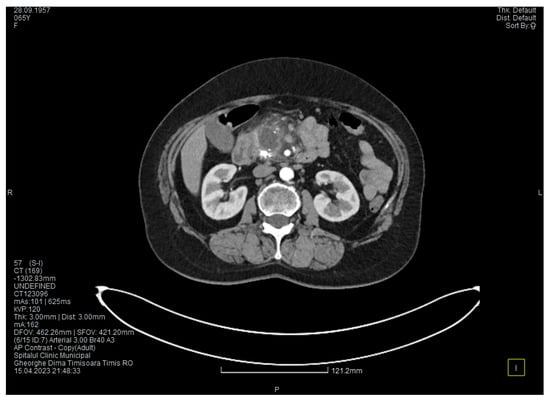

Laboratory tests showed a serum lipase level more than 10 times above the upper normal range. The contrast-enhanced computed tomography (CT) showed multiple calcifications in the pancreatic tissue, dilatation of the main pancreatic duct measuring approximately 12.5 mm (Figure 1), a non-iodophilic intraparenchymal cyst in the head of the pancreas measuring 23/25 mm, which was associated with acute inflammation (Figure 2), and densification of the peripancreatic fat, which was more intense at the head of the pancreas. In addition, enlarged pericephalic and periaortocaval lymph nodes were observed. There were no changes in the liver or the gallbladder, only a mild ectasia of the intrahepatic bile ducts, and no dilatation of the common bile duct. Other changes included multiple atheromas of the abdominal aorta. The symptoms, the lab results, and the CT findings led to the diagnosis of acute pancreatitis.

The contrast-enhanced computed tomography showed changes suggestive of chronic pancreatitis, with multiple very small calcifications of the pancreatic tissue, dilatation of the Wirsung duct in the corporeo-caudal area measuring approximately 15 mm (Figure 3), and a narrowing of the Wirsung tract in the cephalic area where calcareous conglomerates were present. In the anterior cephalo-uncinate area, an oval cyst measuring 31/28 mm was detected (larger than it was one month ago) (Figure 4). In the peri-cephalo-uncinate area, we observed densifications of the adjacent fat extending towards the gastric antrum, the root of the mesentery, and the hepatic flexure of the colon. There was a mild inflammatory enlargement of the peripancreatic lymph nodes and the ones situated in the hepatic hilum. We also noticed a slight dilatation of the intrahepatic bile ducts and the common hepatic duct, and diffuse atheromatosis of the aorta, the iliac, and the common hepatic arteries. We performed a gastroscopy, which revealed a normal esophagus, stomach, and duodenal bulb; however, it was impossible to advance the endoscope towards the D2 part of the duodenum due to the significant edema of the duodenal mucosa and the partial stenosis of the duodenal lumen.

Figure 1. The initial CT scan shows a dilated Wirsung duct and calcifications in the pancreatic tissue.

Figure 3. The second CT evaluation shows a dilated Wirsung duct and calcifications in the pancreatic tissue.